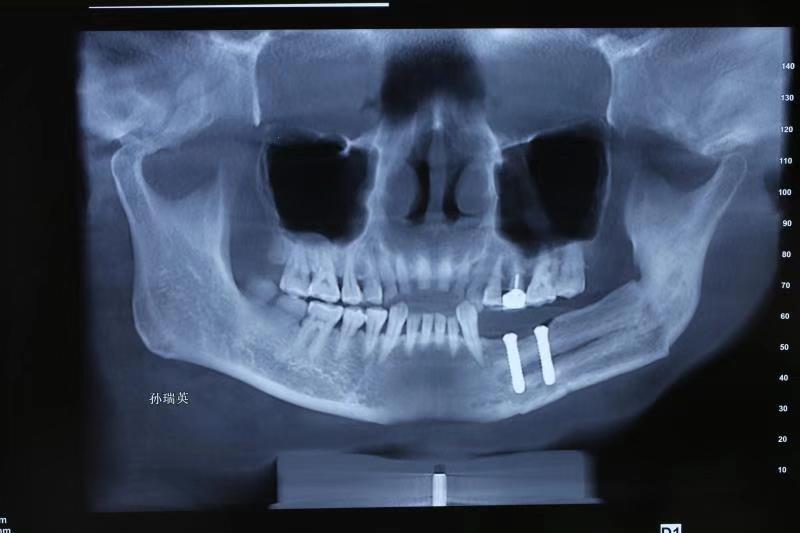

二、针对肿瘤、创伤治疗术后的复杂颌骨、牙列以及软组织缺损,采用种植技术联合骨移植进行功能性重建,尽最大程度恢复患者的咀嚼、发音以及吞咽等口腔功能,提高患者生存质量。(图为下颌骨区段缺损游离腓骨肌皮瓣移植术后行牵引成骨,二期种植行种植修复。